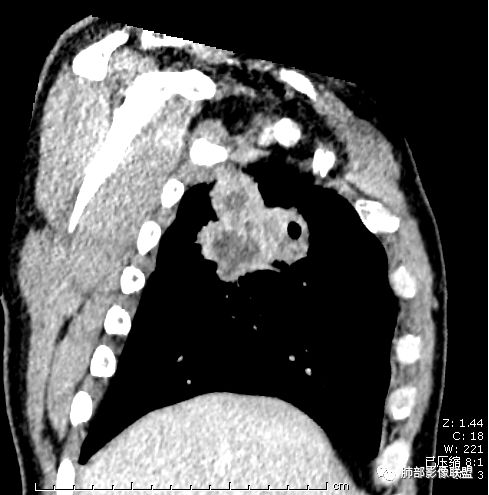

首先病灶示:跨尖、后、前三段,局部突入中叶;大家理解一下:是不是光滑的地方有叶裂,毛糙的地方没叶裂。

这个病变两侧受叶裂的局限,中央没有,如果是穿透叶裂的是否边缘也毛糙?事实上这叶裂边缘的叶裂是很光滑的,我倾向于这个是局部叶裂有缺陷;就是从缺陷处进来有病灶的本色:边缘毛糙;附近叶裂的阻挡,边缘光滑;既然怀疑是局部的缺陷就对良恶性没价值。

第二种是局部叶裂畸形或发育不全、有缺陷,病灶经缺陷处侵犯蔓延,事实上叶裂缺并非少见,影像观察应当结合冠矢状位。

假如一个病灶直接跨越胸膜侵犯过来,应该边缘都很毛糙,不应该是最突出的地方毛糙,应该是逐步毛糙过去的,充其量越到外面毛糙越少;但事实上今天这个病变是一个很突兀的毛糙,突然间嘎然而止的毛糙;所以这个提示应该是从缺陷处跨过来的;还有今天的这个病例,病灶跨叶的部分对附近的胸膜是推移的,附近的胸膜还是很光滑,但是跨叶的病灶区很毛糙,提示跨叶部分存在胸膜缺陷可能;一般来说恶性肿瘤直接侵犯到对侧还是少的,如果这个地方你怀疑有缺陷,跨胸膜在诊断良恶性价值就不大了。